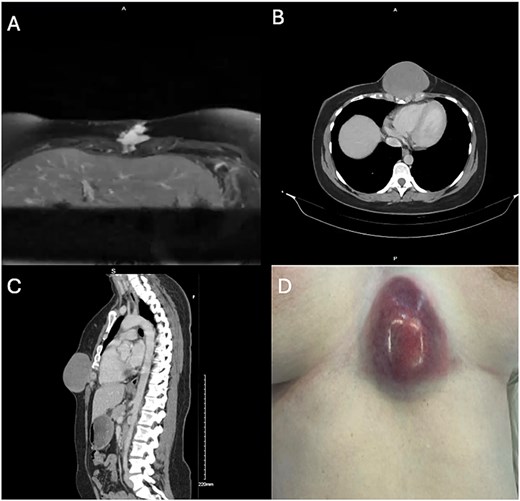

A 34-year-old woman presented with a 3-month history of an enlarging firm lesion over the xiphisternum. There was no history of trauma. MRI demonstrated a 2.2 × 2.5 cm enhancing irregular subcutaneous lesion (Fig. 1A) which on biopsy was suggestive of nodular fasciitis. This was planned for local resection; however, it was deferred as the patient had become pregnant. During her pregnancy, the lesion continued to grow; however, following multidisciplinary discussion, it was felt that the original biopsy was reassuring and likely to represent a benign entity, and thus it was reasonable to continue to wait until after delivery. She had a normal delivery at term. Computed tomography (CT) performed postpartum (Fig. 1B and C) demonstrated an increase in size of the lesion to 8.7 × 8.1 cm. On a physical exam, the lesion had now begun to threaten the overlying skin (Fig. 1D). Given its rapid growth and concern for a more aggressive pathology than original biopsy suggested, an incisional biopsy was taken under general anesthetic instead of outright resection. This revealed a diffuse storiform growth pattern with myxoid stroma, smooth muscle actin positivity, and β-catenin positivity, leading to a diagnosis of a desmoid tumor.

A: MRI axial plane. T2 weighted image. B, C: Non-contrast CT, axial and sagittal planes. D: Photograph of tumor at time of incisional biopsy.